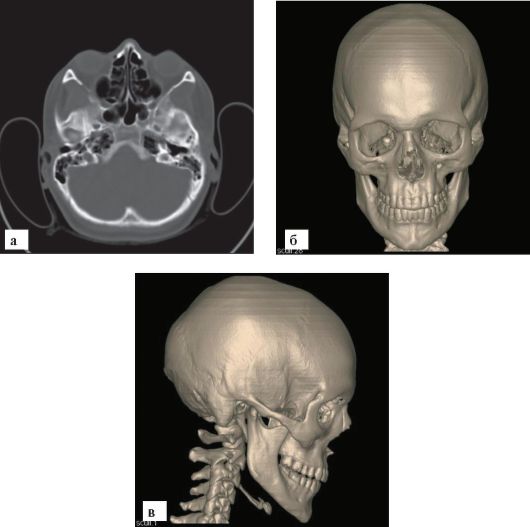

Рис. 3-5. МСКТ черепа:

а - поперечный срез; б - трехмерная реконструкция, вид спереди; в - трехмерная реконструкция, вид сбоку

Более широкие возможности для изучения костей черепа представляет КТ. В современных МСКТ фронтальные и сагиттальные срезы реконструируются из набора аксиальных (рис. 3-5). Преимуществом КТ является не только отсутствие суммации теней, но и наличие воз-

можности изучения всех тканей данного уровня, включая вещество головного мозга.